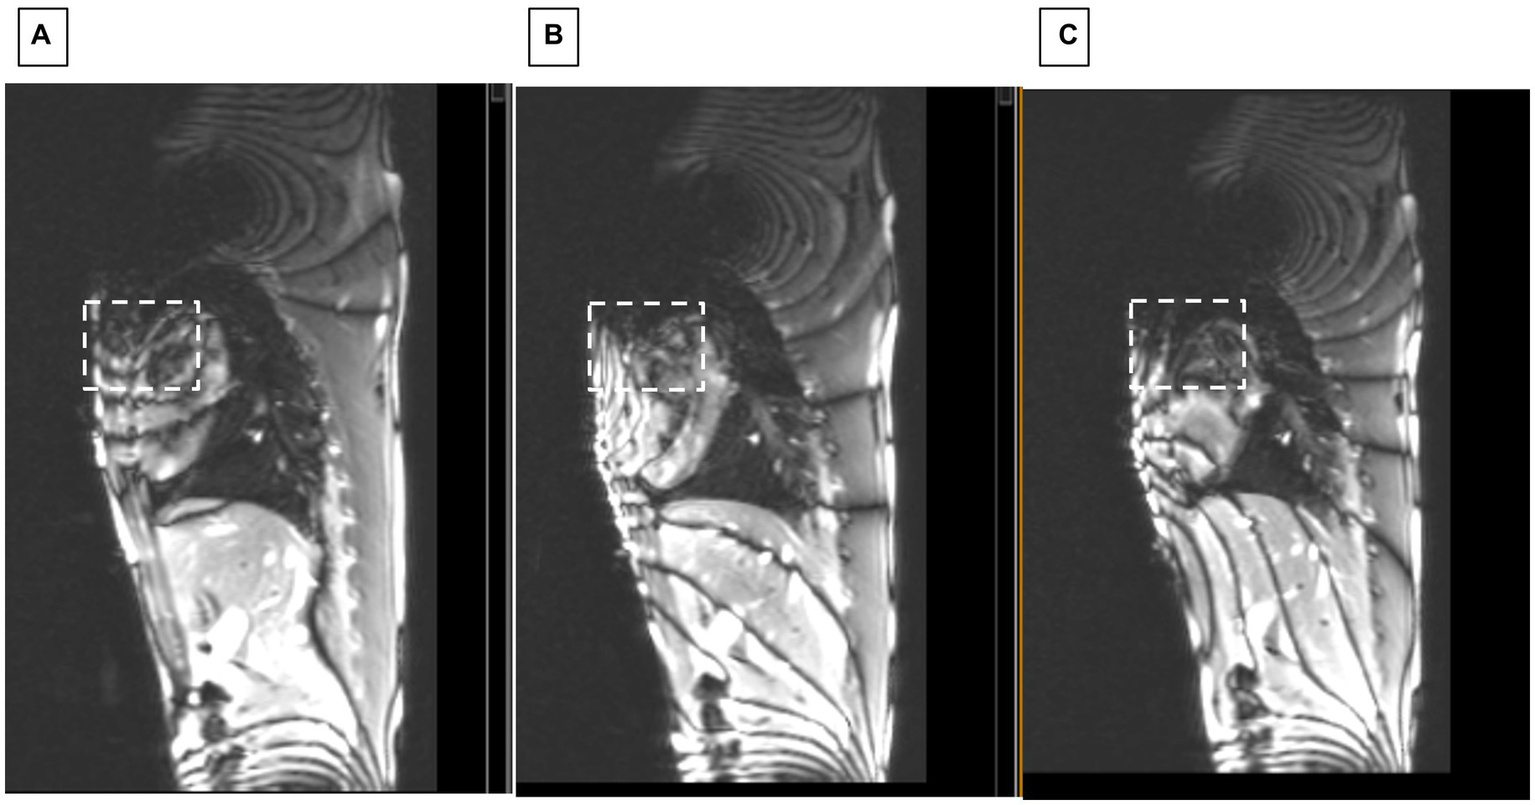

Figure 7

Sagittal SSFP of swine with ICD. Showing changes at applied shim currents of (A) 0, (B) 2.5, and (C) 3.5 Amperes. White dashed square indicates region where homogeneity progressively improved.